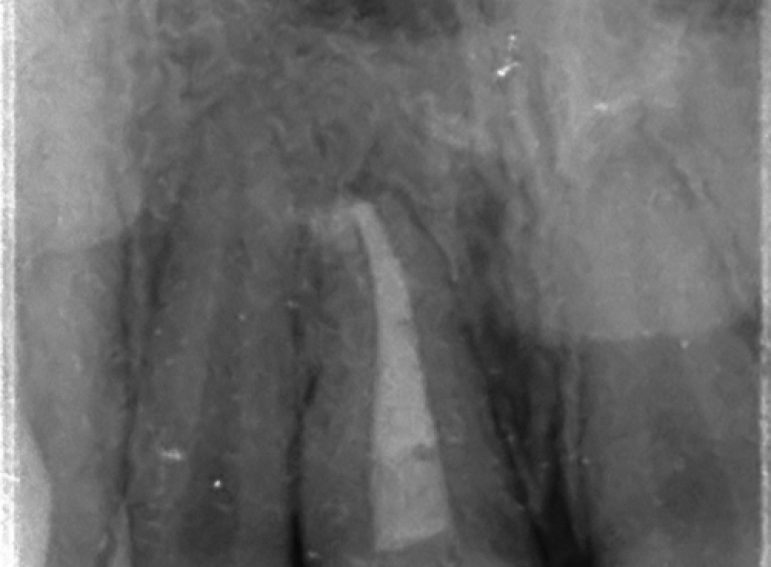

Case 5 – Dental Trauma

Severe Intrusion during braces